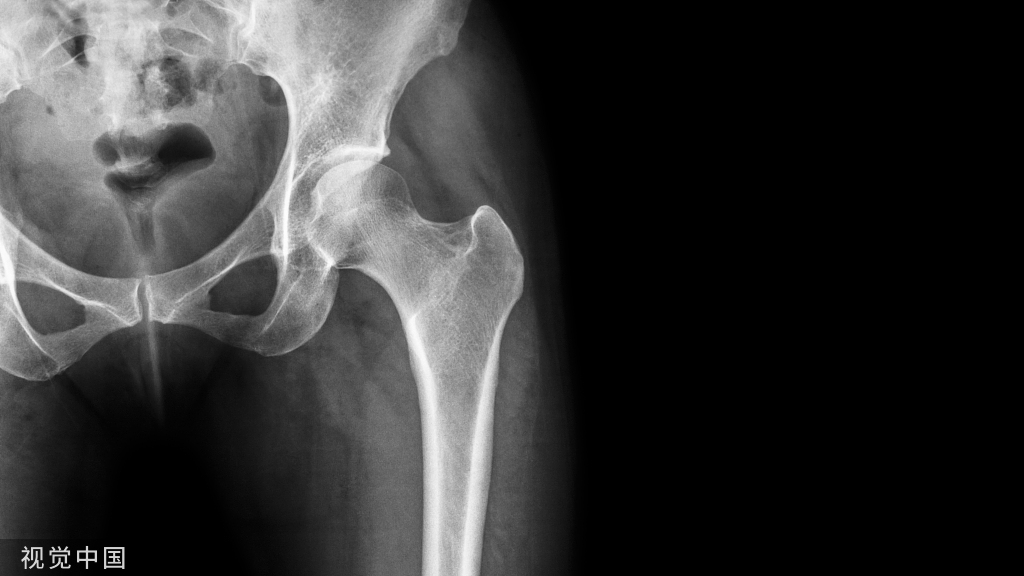

股骨颈骨折的medial buttress

垂直型股骨颈骨折(Pauwels III型)常因垂直剪力大、常规三枚平行空心钉固定易致内固定失败,单纯空心钉+第四枚垂直螺钉或medial buttress 钢板可起到对抗垂直剪力的防滑、支撑作用。